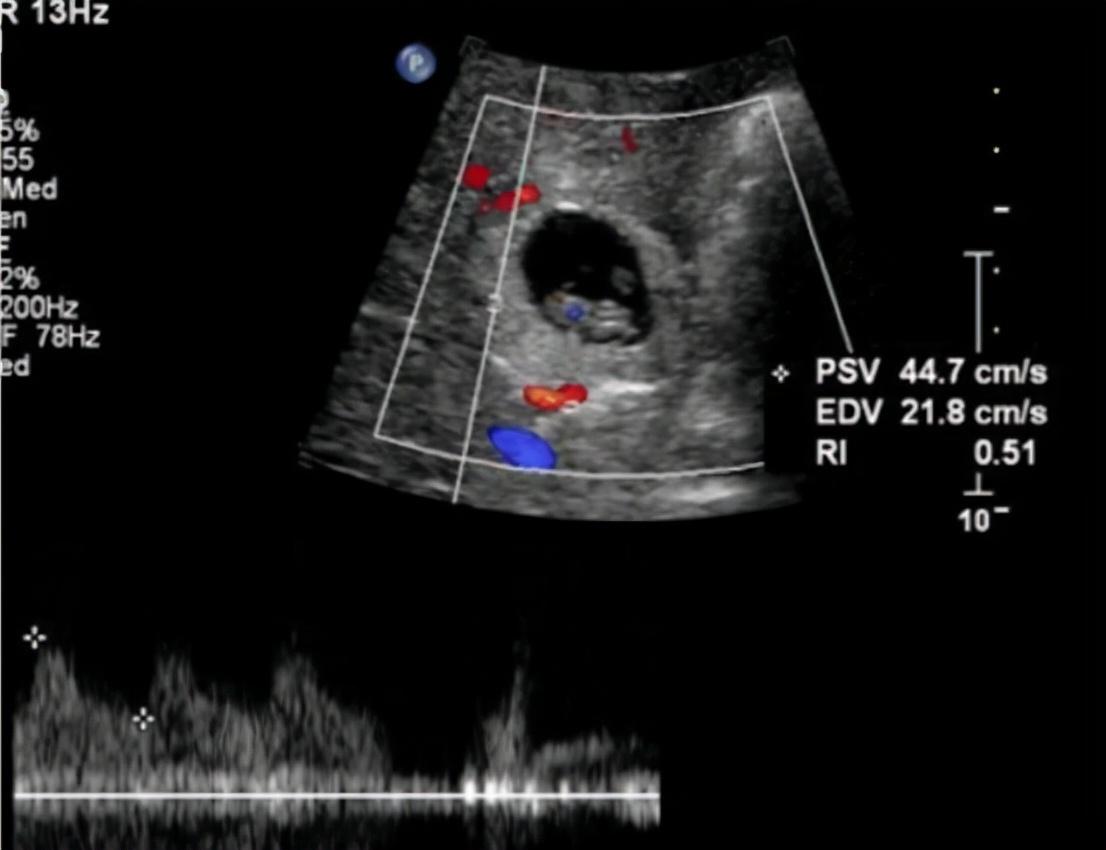

说起来,肝脏妊娠是属于“异位妊娠”的一种,简单来说,就是宫外孕,只不过,肝脏妊娠是最罕见的宫外孕之一,毕竟,谁也想不到,胎儿还能出现在肝脏里,变成“心肝宝贝”。

对此,研究认为,是因为输卵管畸形或者是发炎,导致受精卵无法成功进入子宫,于是,就会落在子宫外面,而在一些比较特殊的情况下,竟然也会跑到了肝脏里,将肝脏当做了子宫,在里面发育了起来。

而且受精卵在肝脏中着床之后,竟然还可以像在子宫中一样,不断来吸取营养,然后不断发育,但是,由于肝脏毕竟和子宫不同,所以,如果没有及时发现,任由胎儿在肝脏中发育,等到胎儿4-5个月的时候,就会将肝脏撑破。